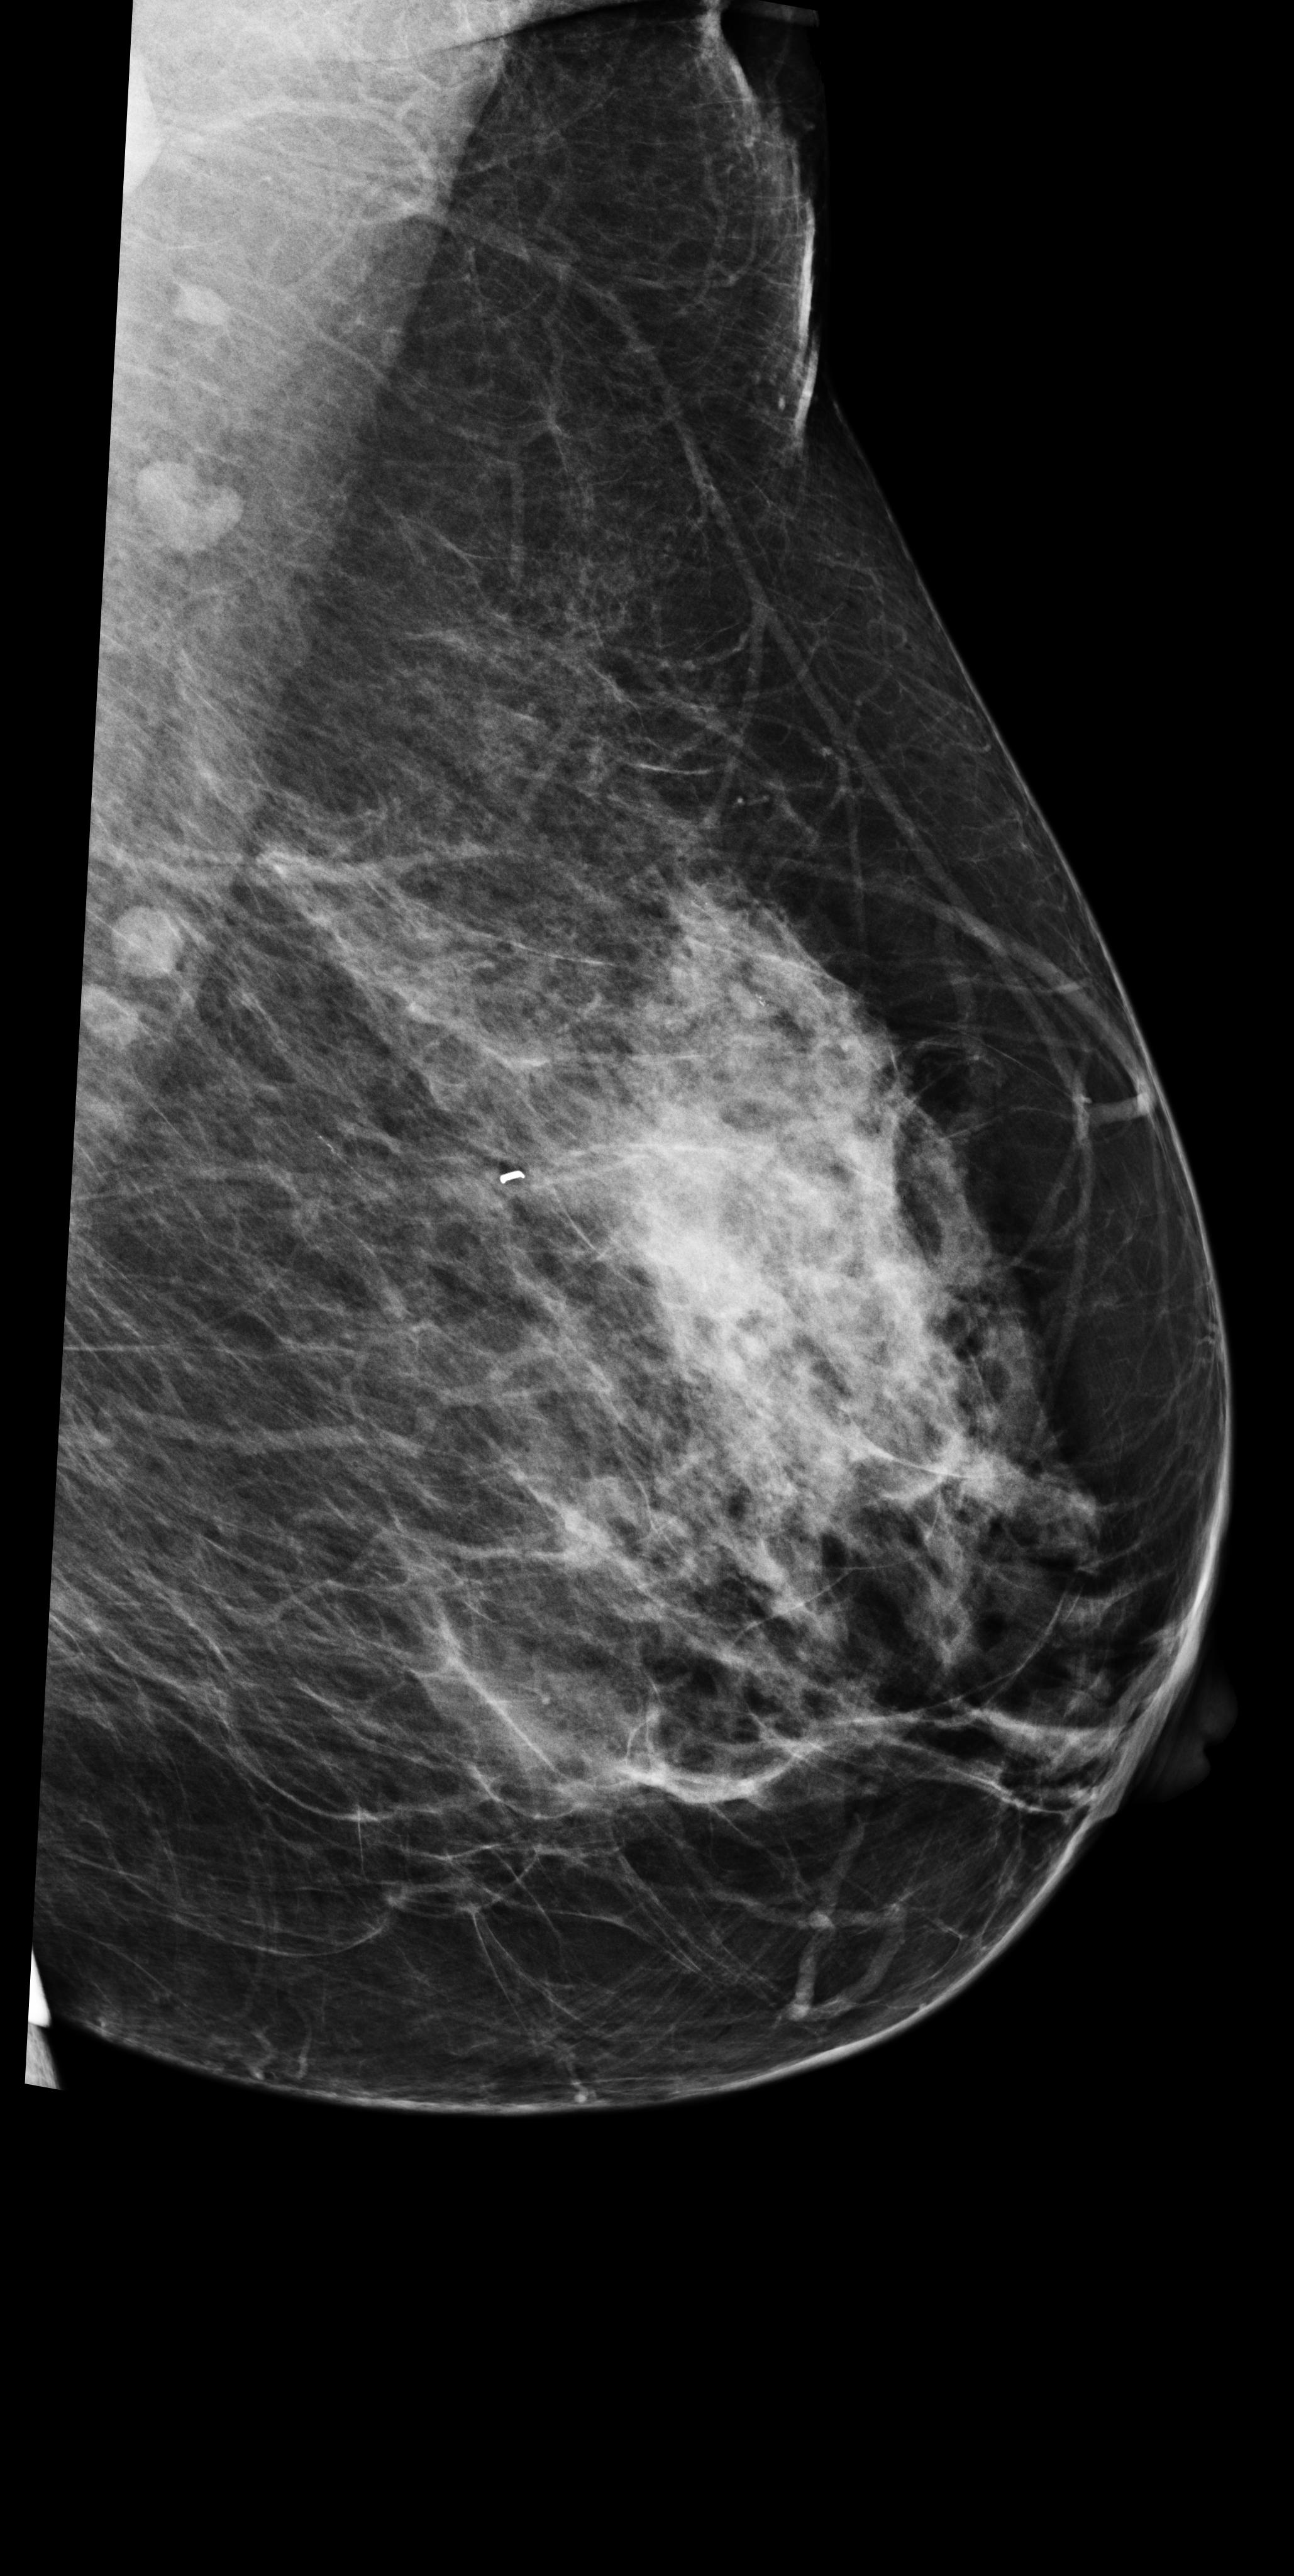

The results from all three models are shown in \tablereftab:example. AlignLocalCompare performs better for malignant prediction than the single-exam baseline and GlobalCompare, in both the biopsied and screening populations. We do not observe improvement for benign category–we speculate that this is because our model learns to focus on regions with significant changes, but not many changes accompany benign findings. In \figurereffig:exams, we visualize a few cases where the AlignLocalCompare is more confident in its prediction than the single-exam baseline Wu et al. (2019a). For \figurereffig:exams(a), we observe that the malignant region did not exist in the prior exam. For \figurereffig:exams(b), we observe that the bright spot at the center already existed in the prior exam, and the model can be more sure that it is not malignant.

[\capbeside\thisfloatsetupcapbesideposition=left,top,capbesidewidth=6cm]figure[13cm] prior latest highlight prior latest L-CC Refer to caption Refer to caption Refer to caption L-CC Refer to caption Refer to caption L-MLO Refer to caption Refer to caption Refer to caption L-MLO Refer to caption Refer to caption (a) (b)

Figure 3: Test examples where AlignLocalCompare performs better than the single-exam baseline. A breast with a malignant finding shown in (a) (malignant finding is highlighted with red) and one with a benign lesion shown in (b). AlignLocalCompare predicts malignancy with 0.97 probability for (a) and 0.04 for (b), whereas the baseline predicts 0.73 for (a) and 0.24 for (b). There is about a year gap between two exams for both patients.